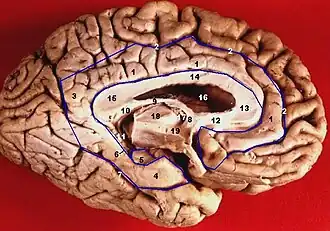

![]() Medial surface of left cerebral hemisphere. Uncus is shown in orange. | |

Human brain inferior-medial view (Uncus is #5) | |